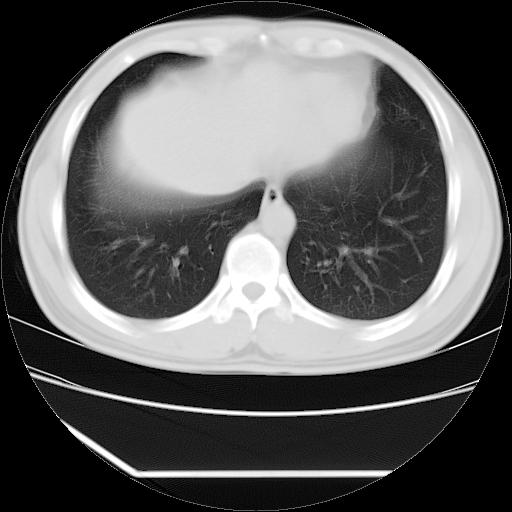

男,38岁,于2009年8月9日晚突发左侧胸痛,今x线提示左下肺阴影,为了明显确诊断,行ct检查,

血常规:嗜酸性细胞增高,单核细胞增高。

病灶发生在下叶,密度均匀,边缘模糊、毛糙,周围血管纹理增强扭曲改变,靠近胸膜处病灶胸膜反应明显。

支持考虑---球形肺炎。

左肺舌叶病变。主体病灶呈类圆形中心密度低,成液化趋势周边班片影分布

考虑肺脓肿

虽然实验室检查支持炎性病变,且病变内有坏死改变(中央呈大片状低密度影),但仍不能掉以轻心,鳞癌也可以有这种影像改变。